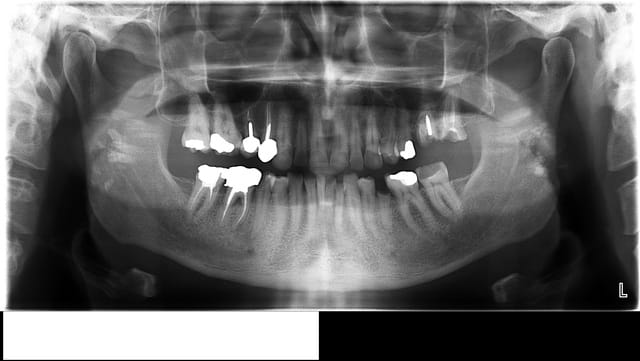

Patient âgé de 50 ans, médecin, vient en consultation pour des douleurs mandibulaires droites, irradiantes, à la pression et abcès qui ont été traité par des antibiotiques régulièrement (auto médication sans consultation de chir dent depuis des années).

L’observation clinique et radiologique révèle :

- Sourire gingival

- Supracclusion

- Bruxisme +++

- 47 amalgame OMD + traitement endo incomplet + fracture pan lingual sous gingival

- 46 couronne coulée, atteinte furcation, suppuration

- 45 carie OD, nécrose, lésion apicale

- De 44 à 34 abrasées ++, avec pour 42 41 31 32 une hauteur coronaire de 2-3 mm et un encombrement

- 35 racine

- 36 amalgame OD fracturé et mésio versé

- 37 abrasion Occluso linguale++ et douleur au froid et chaud de temps en temps

- 27 racine + carie

- 26 racine + carie + atteinte furcation

- 25 amalgame OD

- De 24 à 13 abrasion OL +++

- 14 couronne coulée inadaptée

- 15 CCM qui se descelle régulièrement

- 16 amalgame OD

- 17 amalgame O

- Perte de DV liée à la parafonction

- 18 28 38 48 absentes

Une pano a été réalisé, et depuis j’ai du extraire 47 46 et 26.